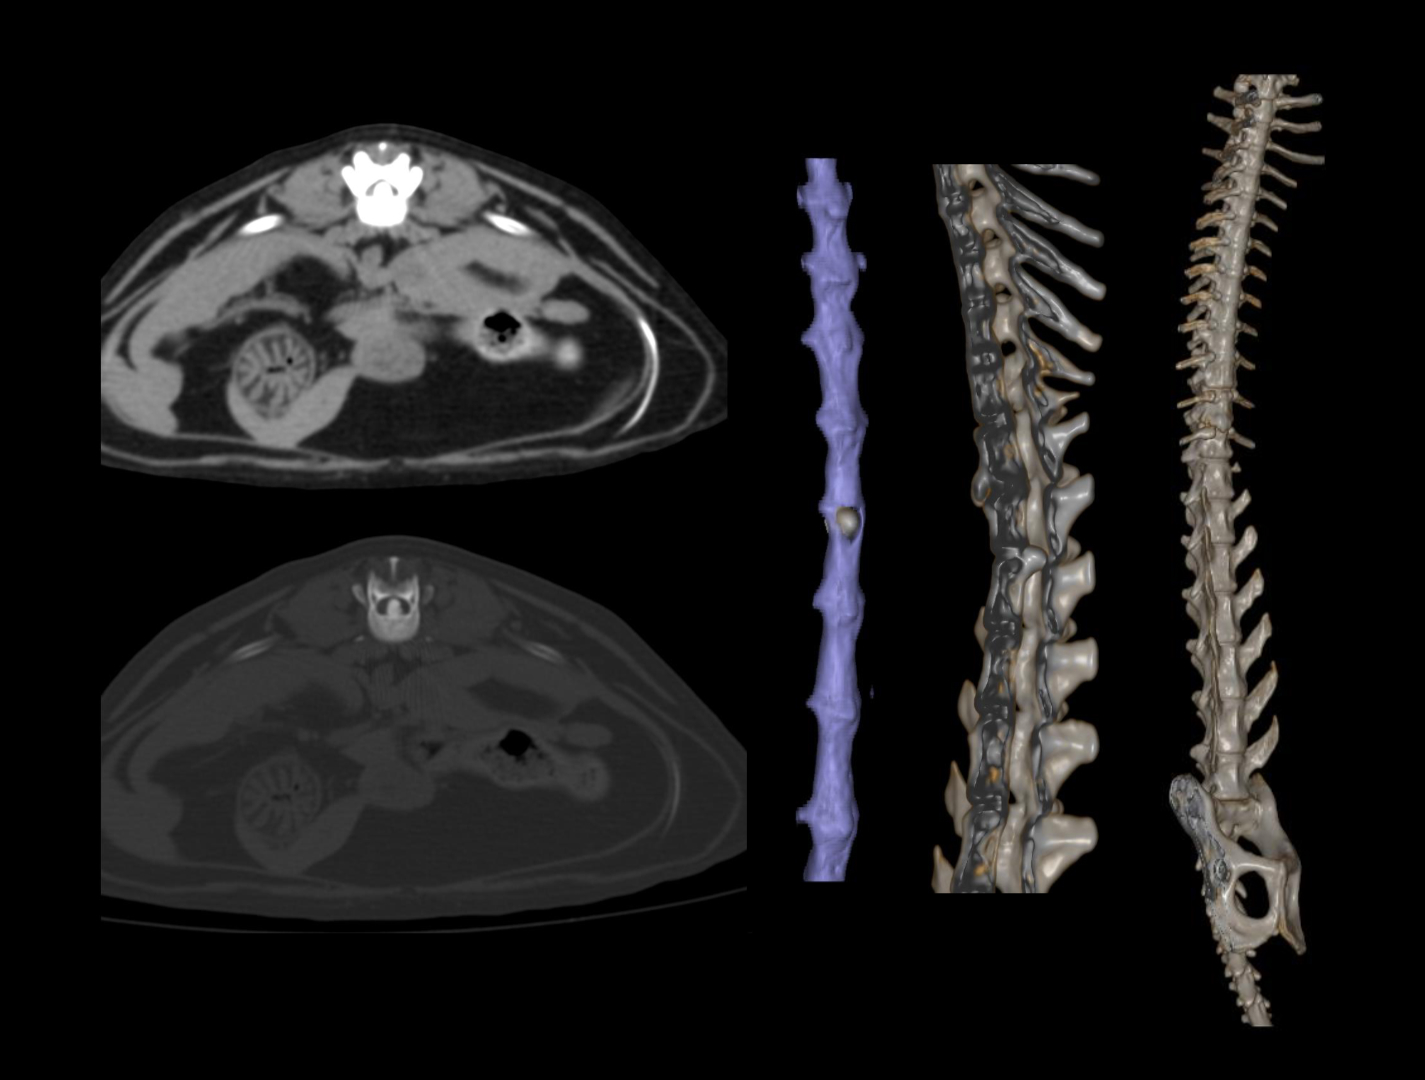

SinoVision AlphaCT 358 Plus — компьютерный томограф на 64 среза. Устройство позволяет получать изображения высокой чёткости с помощью современной интеллектуальной платформы.

Универсальный томограф AlphaCT 358 Plus позволяет получать изображения высокой чёткости.

Виртуальная эндоскопия, позволяющая воссоздать внутреннюю структуру полых органов животных, что может быть актуально, например, при планировании предстоящей операции.

• 64 среза

• Толщина среза от 0,3125 мм

• Интеллектуальная система обработки изображения

• Патентованный детектор V-PIXEL